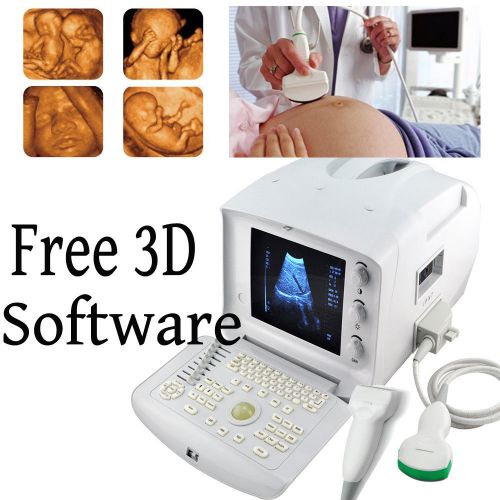

Portable Ultrasound Scanner handheld Digital machine 3.5 Convex,CMS600S promotio

3D Portable Digital Ultrasound Scanner system Micro-Convex Linear Probe

3D PC Based Full Digital Build in 3D Ultrasound Scanner + Linear probe FDA CE

3D Portable Ultrasound Scanner machine system Convex+Linear USB FDA CE

CONTEC CMS600P2 notebook type B-ultrasound System wirh free convex probe.3.5mhz

PC Platform Digital Laptop Ultrasound Scanner Convex + TV 2 Probes FDA CE PASS

FDA Digital Portable diagnose Ultrasound Scanner machine convex+ 3D BUY#